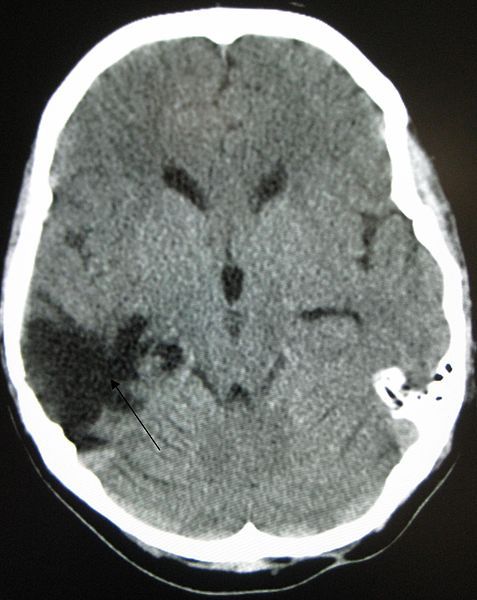

Unfortunately, many traumatic brain injuries are made worse when you do not seek medical treatment right away. Swelling of the brain or bleeding may have disabling or even fatal results hours or days after the initial trauma occurs.